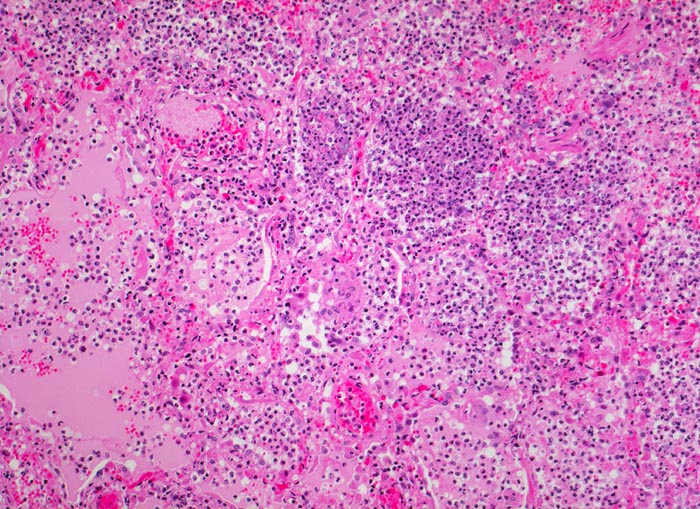

Bronchopneumonie: pneumonisches Infiltrat

Pneumonisches Infiltrat: die Alveolen sind gefüllt mit neutrophilen Granulozyten und rosafarbener Ödemflüssigkeit. Die Alveolarkapillaren sind hyperämisch.

Ödem und Gefässhyperämie sind Zeichen der akuten Entzündung und nicht Ausdruck einer akuten Lungenstauung.

Histologie

100